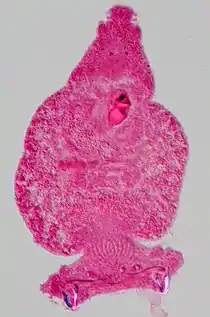

| Tinción de Grocott | Detección de microorganismos, en especial fúngicos. | ![]() | ||